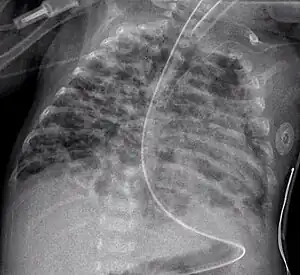

Chest film showing increased opacity in both lungs, indicative of pneumonia

A chest radiograph showing bronchopulmonary dysplasia.